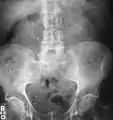

Calcium-containing stones are relatively radiodense, and they can often be detected by a traditional radiograph of the abdomen that includes the kidneys, ureters, and bladder (KUB film).[58] KUB radiograph, although useful in monitoring size of stone or passage of stone in stone formers, might not be useful in the acute setting due to low sensitivity.[59] Some 60% of all renal stones are radiopaque.[60][61] In general, calcium phosphate stones have the greatest density, followed by calcium oxalate and magnesium ammonium phosphate stones. Cystine calculi are only faintly radiodense, while uric acid stones are usually entirely radiolucent.[62]

Bilateral kidney stones can be seen on this KUB radiograph. There are phleboliths in the pelvis, which can be misinterpreted as bladder stones.